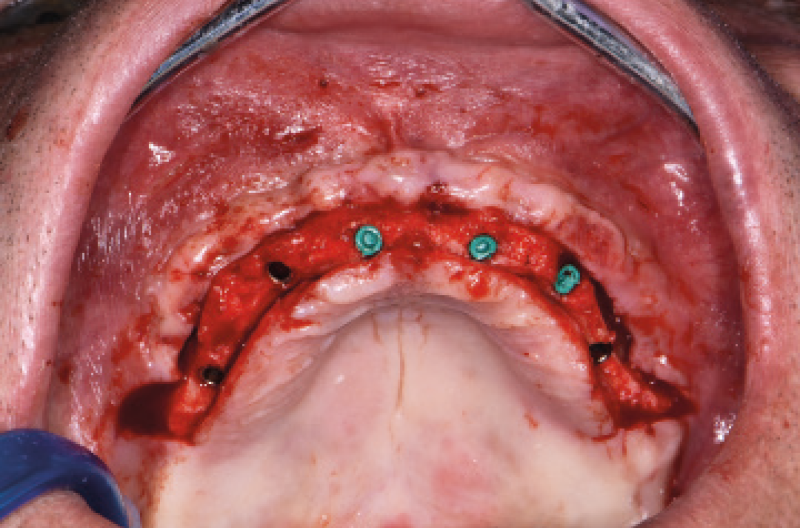

Nel mese di luglio 2019 il paziente ├© stato operato con il contestuale inserimento di 10 impianti, 4 nellŌĆÖarcata inferiore e 6 nellŌĆÖarcata superiore. Ho inserito 4 impianti Max Stability ├ś 3,75 mm nella zona della premaxilla, uno lungo 10 mm e gli altri tre da 12 mm di lunghezza; in regione 15 e 25 ho dovuto invece utilizzare delle frese da osseodensificazione per compattare lŌĆÖosso e traslare la parete mediale del seno mascellare per poter inserire 2 impianti Max Stability ├ś 3,75 L 12 mm inclinandoli lungo la parete stessa. Data la scarsa quantit├Ā e qualit├Ā di osso nel mascellare, ho rinunciato al carico immediato rinviando la procedura della protesizzazione immediata nella fase di riapertura degli impianti ad osteointegrazione avvenuta (Figg. 1-14).

Fig. 12 – Posizionamento dei tappi di chiusura

Fig. 13 – Innesto di osso autologo

Fig. 14 – Sutura

Ho riaperto il mascellare superiore con un lembo a spessore parziale palatino e con scarichi solo distali per limitare al minimo il trauma allŌĆÖosso perimplantare; dopodich├® ho scelto i monconi MUA pi├╣ idonei, tutti GH 1,5 mm uno diritto, tre angolati a 15┬░ e due angolati a 25┬░. Una volta parallelizzati, ho attivato i monconi MUA negli impianti e avvitato gli adattori Conic per trasformarli in monconi MUA-Conic. Dopo aver suturato il lembo, ho attivato le cappette Fixed sui monconi MUA-Conic e poi si ├© proceduto alla ribasatura della protesi opportunamente scaricata in corrispondenza dei monconi MUA-Conic. Durante la procedura intraorale di inglobamento delle cappette Fixed, la protesi si ├© autocentrata in occlusione con la protesi conometrica fissa provvisoria inferiore. Infine la protesi ├© stata rifinita, riposizionata in bocca e attivata (Figg. 30-37). A distanza di un mese entrambe le Toronto provvisorie sono state rimosse e ribasate per un migliore condizionamento del tessuto gengivale (Fig. 38).

Fig. 34 – Vista occlusale dei monconi MUA-Conic